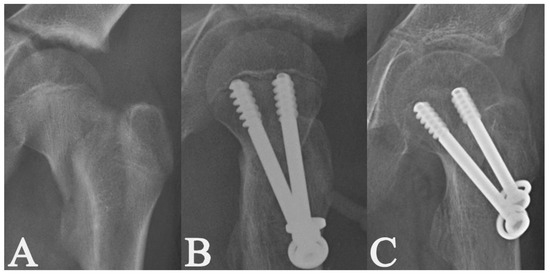

| Fixation method | Two cannulated screws (n = 100; 75.8%) | 3.1 ± 1.6 | 0.919 | 0.360 |

| Three cannulated screws (n = 32; 24.2%) | 3.4 ± 1.5 | |||